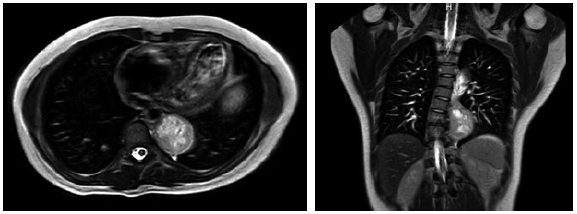

Presenta un cuadro clínico de cefalea holocraneana diaria e intermitente, de instauración gradual, de tipo pulsátil e intensidad moderada, que está acompañada de taquicardia y diaforesis, lo cual inició seis meses antes de su admisión, sin exacerbantes o atenuantes. El monitoreo ambulatorio de presión arterial reveló hipertensión arterial sistólica y diastólica de día y de noche, por lo que inició el tratamiento actual. Se realizó una pesquisa de hipertensión arterial secundaria, incluyendo una resonancia magnética de abdomen contrastada, bajo sospecha de TNE suprarrenal. Se evidenciaron signos de neoformación en mediastino posterior, con diámetros de 43 x 38 x 59 mm, en situación paravertebral izquierda (figura 1).

Resonancia magnética de abdomen Nota: A Imagen hiperintensa localizada en mediastino posterior. B. Imagen de aspecto fusiforme, heterogénea, hiperintensa en t1, con focos hiperintensos en t2 y periferia de menor intensidad de señal que realza predominantemente en la periferia, con diámetros de 43 x 38 x 59 mm.

Figura 1: Resonancia magnética de abdomen Nota: A Imagen hiperintensa localizada en mediastino posterior. B. Imagen de aspecto fusiforme, heterogénea, hiperintensa en t1, con focos hiperintensos en t2 y periferia de menor intensidad de señal que realza predominantemente en la periferia, con diámetros de 43 x 38 x 59 mm.

Fuente: elaboración propia.